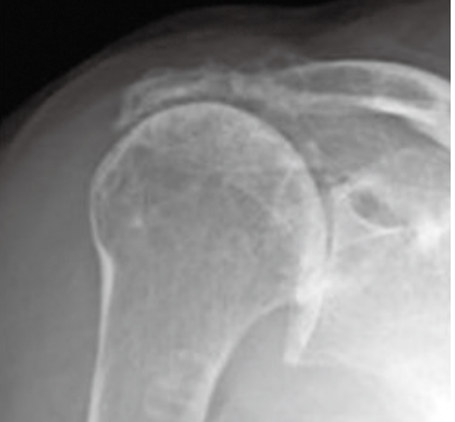

1.X線(レントゲン)検査

骨の状態を確認するために行われます。腱板自体はX線には写りませんが、骨棘(骨のトゲ)の形成や、上腕骨頭の挙上(腱板機能不全による)など、腱板断裂を示唆する間接的な所見が得られることがあります。断裂サイズが大きくなり不安定性が持続したまま上肢を動かしていくと、次第に骨頭が変形して2次性の変形性肩関節症であるcuff tear arthropathyとなります(図)。また、肩関節の他の疾患(変形性肩関節症など)との鑑別にも役立ちます。

図:Cuff tear arthropathyのレントゲン/広範囲断裂のMRI

出典:横矢 晋. (2024). 腱板断裂のリハビリテーション―保存加療から術後後療法を含めて―. MB Med Reha, 304, 44-51.